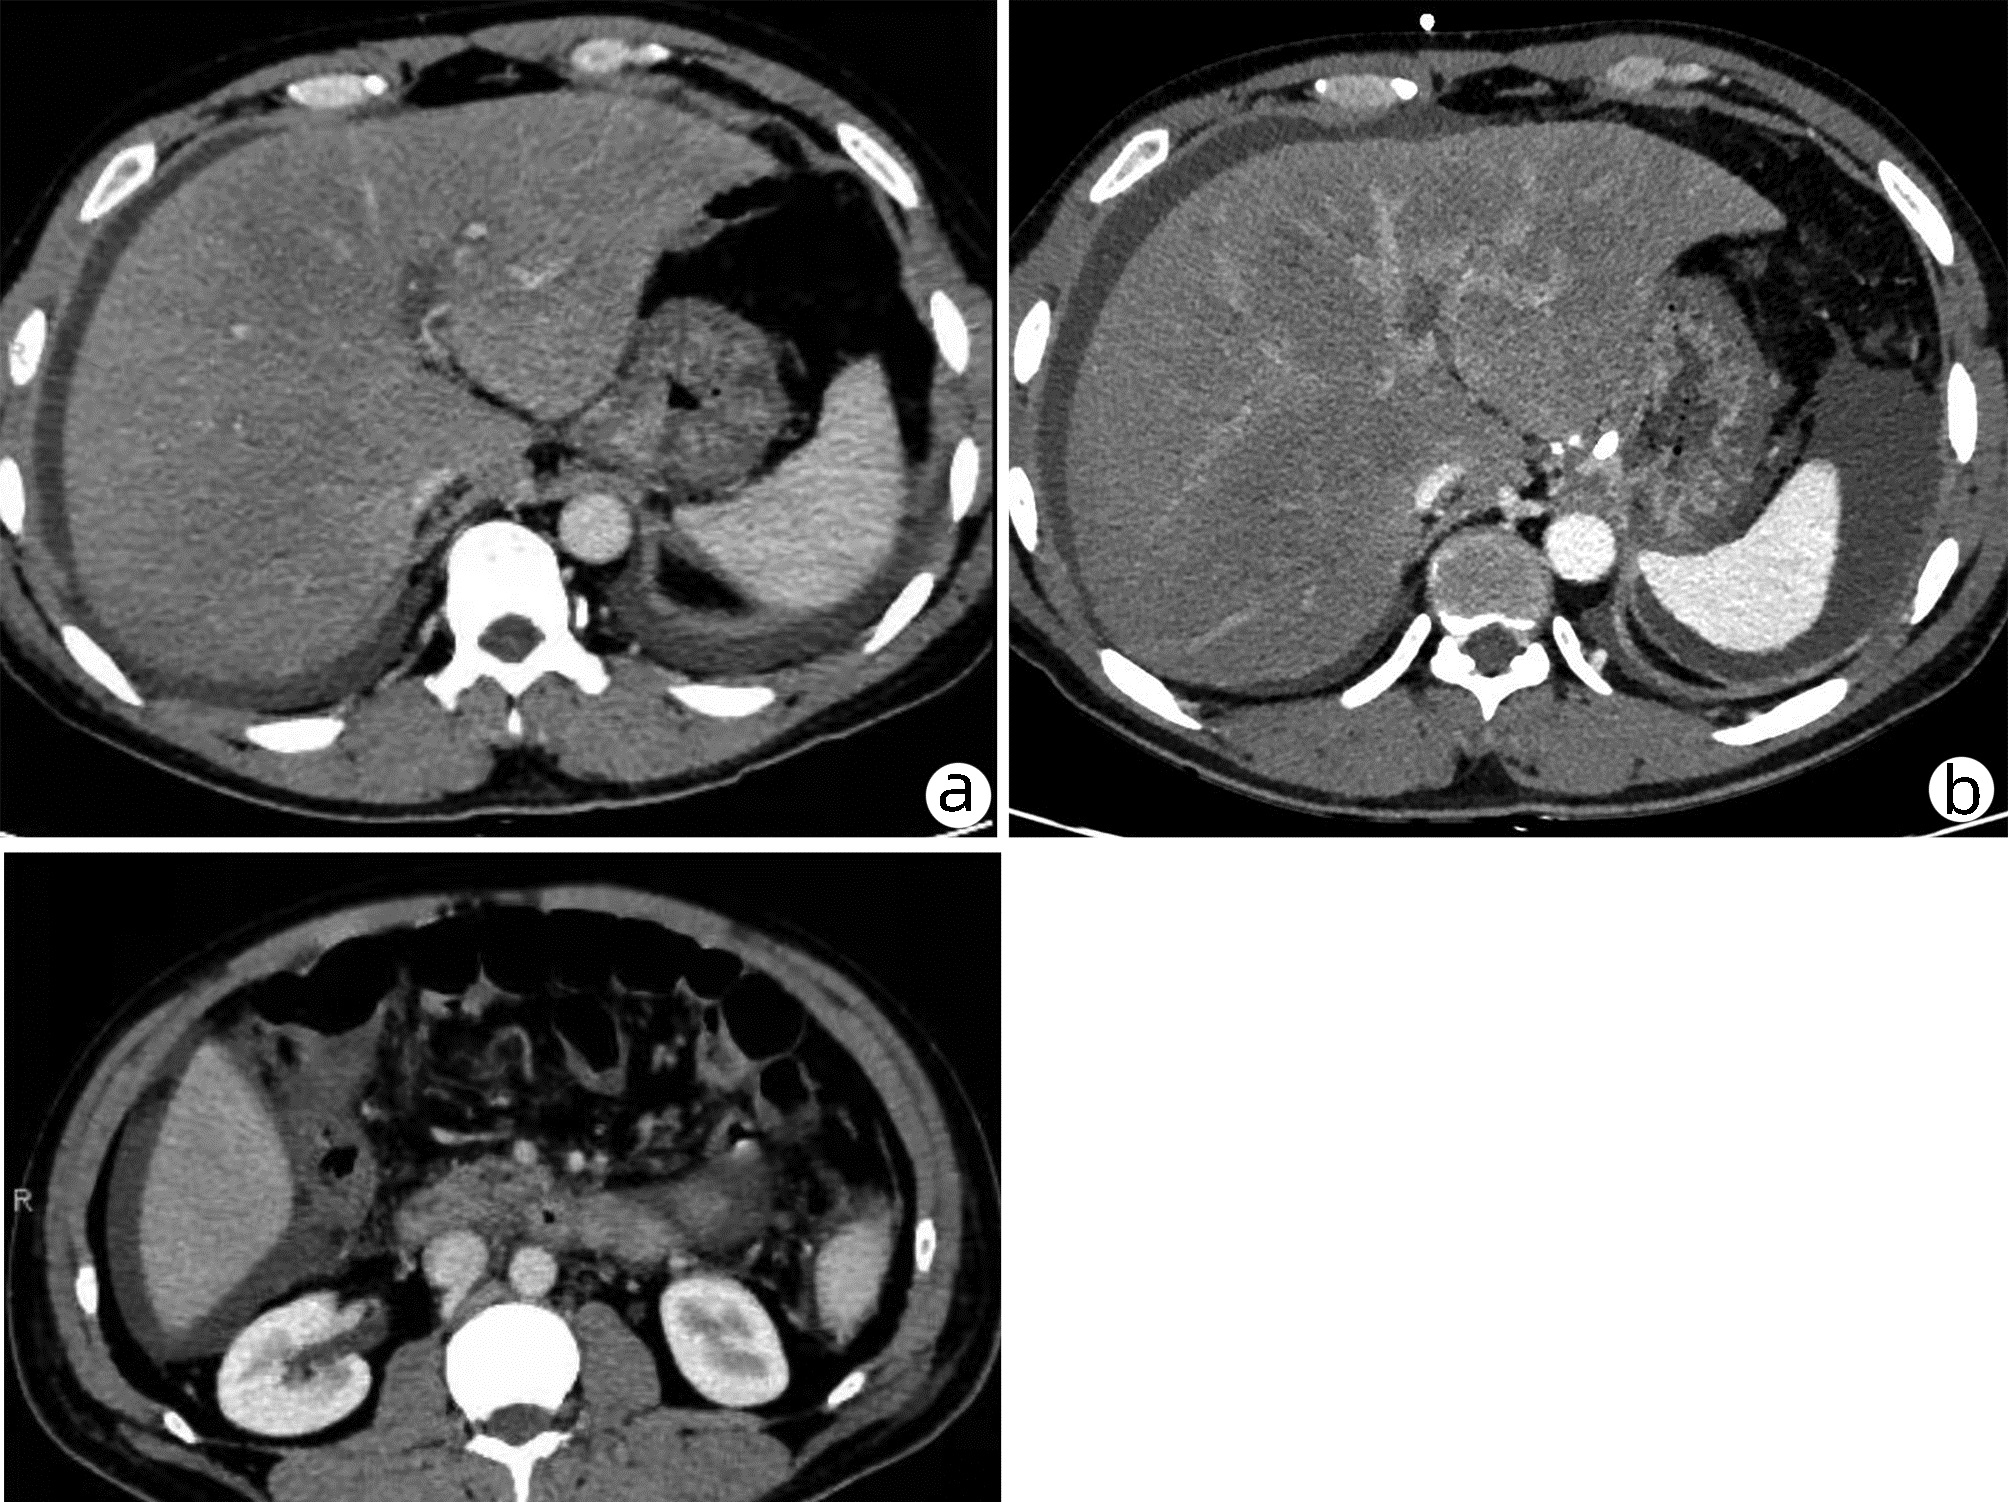

Risk factors of rebleeding after endoscopic treatment of patients with portal vein tumor thrombus and esophagogastric variceal bleeding

Xiuxia LIANG, Lingling HE, Junru YANG, Fuyang ZHANG, Jiali MA, Yuling ZHOU, Julong HU, Ping LI, Hongshan WEI

2022, 38(10): 2290-2295. DOI: 10.3969/j.issn.1001-5256.2022.10.017

Abstract(1045) HTML (231) PDF (2924KB)(53)

Abstract:

Objective  To analyze the rebleeding rate in hepatocellular carcinoma (HCC) patients with portal vein tumor thrombus (PVTT) after endoscopic treatment of esophagogastric variceal bleeding and then assessed the risk factors of the rebleeding in the patients.  Methods  This study retrospectively recruited 169 hepatitis B-associated HCC patients complicated with PVTT and esophagogastric variceal bleeding treated by endoscopy in Department of Gastroenterology, Beijing Ditan Hospital from September 2008 to December 2016. Among them, 47 patients had PVTT Ⅱ, 67 patients had PVTT Ⅲ, and 55 patients had PVTT Ⅳ. Their clinicopathological and follow-up data were retrieved from the medical records and statistically analyzed. Continuous data were compared among groups using ANOVA or Kruskal-Wallis H test. Categorial data were compared among groups using Chi-square test or corrected Fisher test. The Kaplan-Meier curves and Log-rank test were performed to analyze the rebleeding rate and cumulative survival rates after treatment. The univariate multivariate Cox regression analyses were used to identify the risk factors affecting the rebleeding of patients.  Results  Compared with PVTT Ⅱ and Ⅲ, PVTT Ⅳ patients had a higher serum level of the direct bilirubin (Z=6.153, P=0.046). The endoscopy treatment successfully blocked esophagogastric variceal bleeding in all patients. There was no significant difference in the rebleeding rates within six months and a year after the treatment (all P > 0.05). It was also no statistically significant difference in cumulative survival rates in six months and l-, 2-, and 3-year after the treatment in PVTT Ⅱ, Ⅲ, and Ⅳ patients (all P > 0.05). Cox multivariate regression analysis showed that hepatic encephalopathy (HR=3.643, 95%CI: 2.099-6.325, P < 0.001), γ-glutamyltransferase (HR=1.002, 95%CI: 1.000-1.005, P=0.029), AFP (HR=1.000, 95%CI: 1.000-1.000, P=0.002) and numbers of tumor lesions (HR=1.647, 95%CI: 1.011-2.684, P=0.045) were all independent risk factors for 1-year rebleeding in these PVTT patients with esophagogastric variceal bleeding after endoscopic treatment.  Conclusion  Endoscopic hemostasis is a feasible treatment option for HCC patients with PVTT and esophagogastric variceal bleeding. However, there was no significant difference in the rebleeding and cumulative survival rates in these patients. Furthermore, hepatic encephalopathy, γ-glutamyltransferase, AFP and numbers of tumor lesions were all independent risk factors for 1-year rebleeding in these patients.